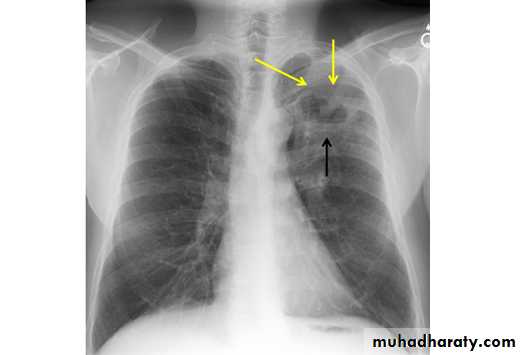

X-ray of pleural effusion

Massive right effusion